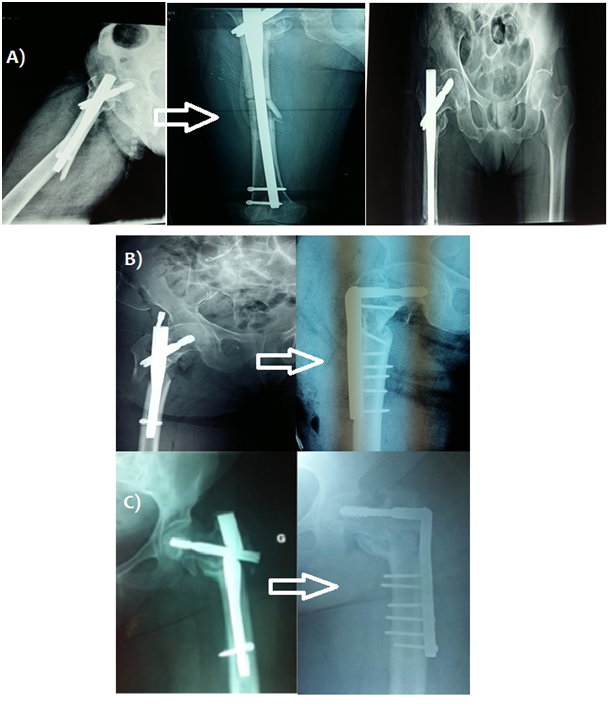

Postoperative complications were observed in 40 patients (8.8%) mainly diaphyseal femoral fractures and cervical screw cut out (Figure 2). 9 cases (2.2%) of proximal third diaphyseal fractures occurred between the 1st and 5th postoperative months with fracture line slightly distal to locking screw or tip of nail. All cases underwent nail removal and revision using long gamma nails in 6 cases and a femur nail in 3 cases with favorable outcome (Figure 3).

Figure 3 A) Revision surgery using a long gamma nail after diaphyseal femur fracture. B) Revision surgery with a 95° dynamic condylar screw after gamma nail failure. C) Revision with a 95 ° condylar screw after implant breakage complicating a case of non-union.

6 cases (1.5%) with cervical screw cut-out were recorded, with immediate postoperative radiography showing bad positioning: cervical screw placement was either too superior or posterior and sometimes even too short. Two cases with acetabular penetration required a total hip arthroplasty, and a single case of revision using a 95 ° dynamic condylar plate screw. A case of early secondary displacement of sub trochanteric fracture treated with standard gamma nail underwent revision using a 95 ° dynamic condylar with a favorable outcome (Figure 3). Two cases (0.5%) that failed to unite underwent revision using the conventional 95° condylar screw plate system. One entailed a sub trochanteric fracture treated with a long gamma nail which required revision surgery after 6 months using a condylar plate screw with iliac crest bone graft. The second case was marked by implant failure and breakage after 5 months requiring revision using conventional dynamic condylar screw system (Figure 3). However, another case of implant breakage with radiological progression of callus was closely monitored and eventually united after 6 months without reoperation (Figure 4).